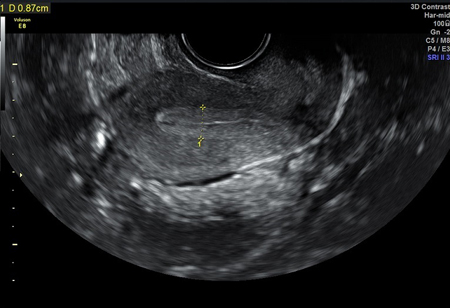

二维超声:观察子宫及双侧卵巢形态和结构变化,对子宫、输卵管、卵巢及盆腔的疾病做基础性排查。